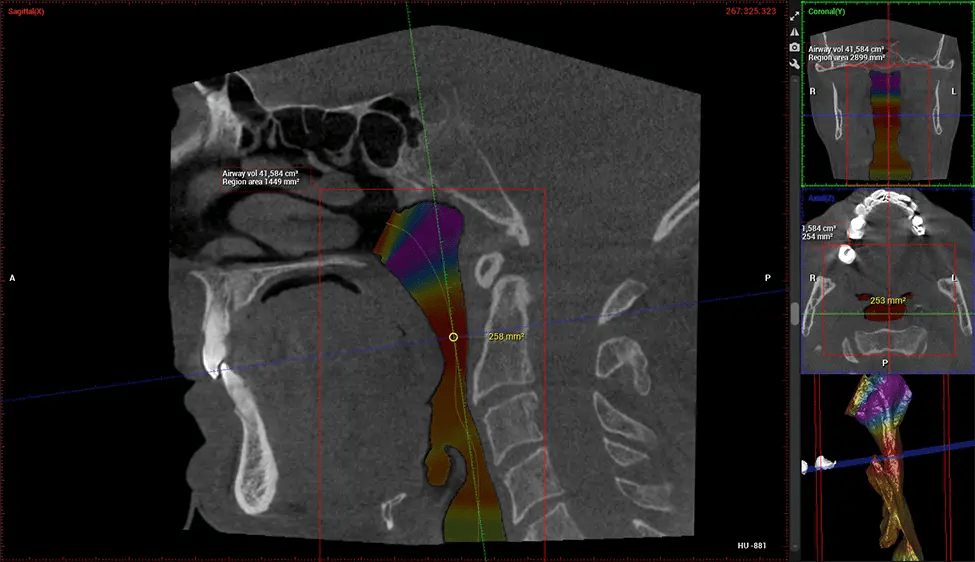

ENT Physician Diagnosing obstructive sleep apnea (OSA) and evaluating sinus and nasal cavity anatomy. Visualizes the entire pharyngeal airway to measure volume, pinpoint constrictions, and plan corrective surgery if needed.

Dental Sleep Medicine Specialist

Screening and treating patients at risk for OSA.

Provides detailed 3D imaging for airway analysis, helping to create and adjust oral appliances and facilitate effective referrals to medical doctors.